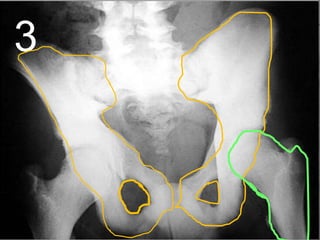

• Your pelvis helps protect the bladder,

intestines, and reproductive organs in

women.